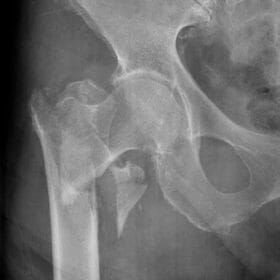

กลไกการเกิดกระดูกหักนั้นเกิดจากแรงกระทำต่อกระดูกที่มากเกินขีดจำกัดที่กระดูกจะทนไหว สาเหตุการเกิดกระดูกหักนั้นอาจมาจากอุบัติเหตุทางการจราจร การตกจากที่สูง หรือจากแรงกระแทกโดยตรงที่กระดูก เช่น การถูกตีการถูกชน เป็นต้น หรือเป็นจากแรงกระทำโดยอ้อม เช่น การหกล้มก้นกระแทกพื้นแล้วเกิดการหักของกระดูกคอสะโพก เป็นต้น กระดูกหักอาจเกิดจากการกระตุกหรือการหดตัวอย่างแรงของกล้ามเน้ือ เช่น การกระโดดแล้วหกล้ม ในท่างอเข่าทำให้กระดูกสะบ้าหัก จากแรงกระชากของกล้ามเนื้อต้นขาและเอ็นสะบ้า

- ข้อเทียม (arthroplasty) ใช้ในกระดูกหักบางชนิดที่ไม่สามารถยึดตรึงได้ เช่นกระดูกคอสะโพกแบบเคลื่อนในผู้สูงอายุ (femoral neck fracture)

- กระดูกตามจากการขาดเลือด (avascular necrosis) ในกระดูกบางบริเวณ ที่มีเลือดมาเลี้ยงน้อย เช่น หัวกระดูกสะโพกและกระดูกทาลัส (talus)